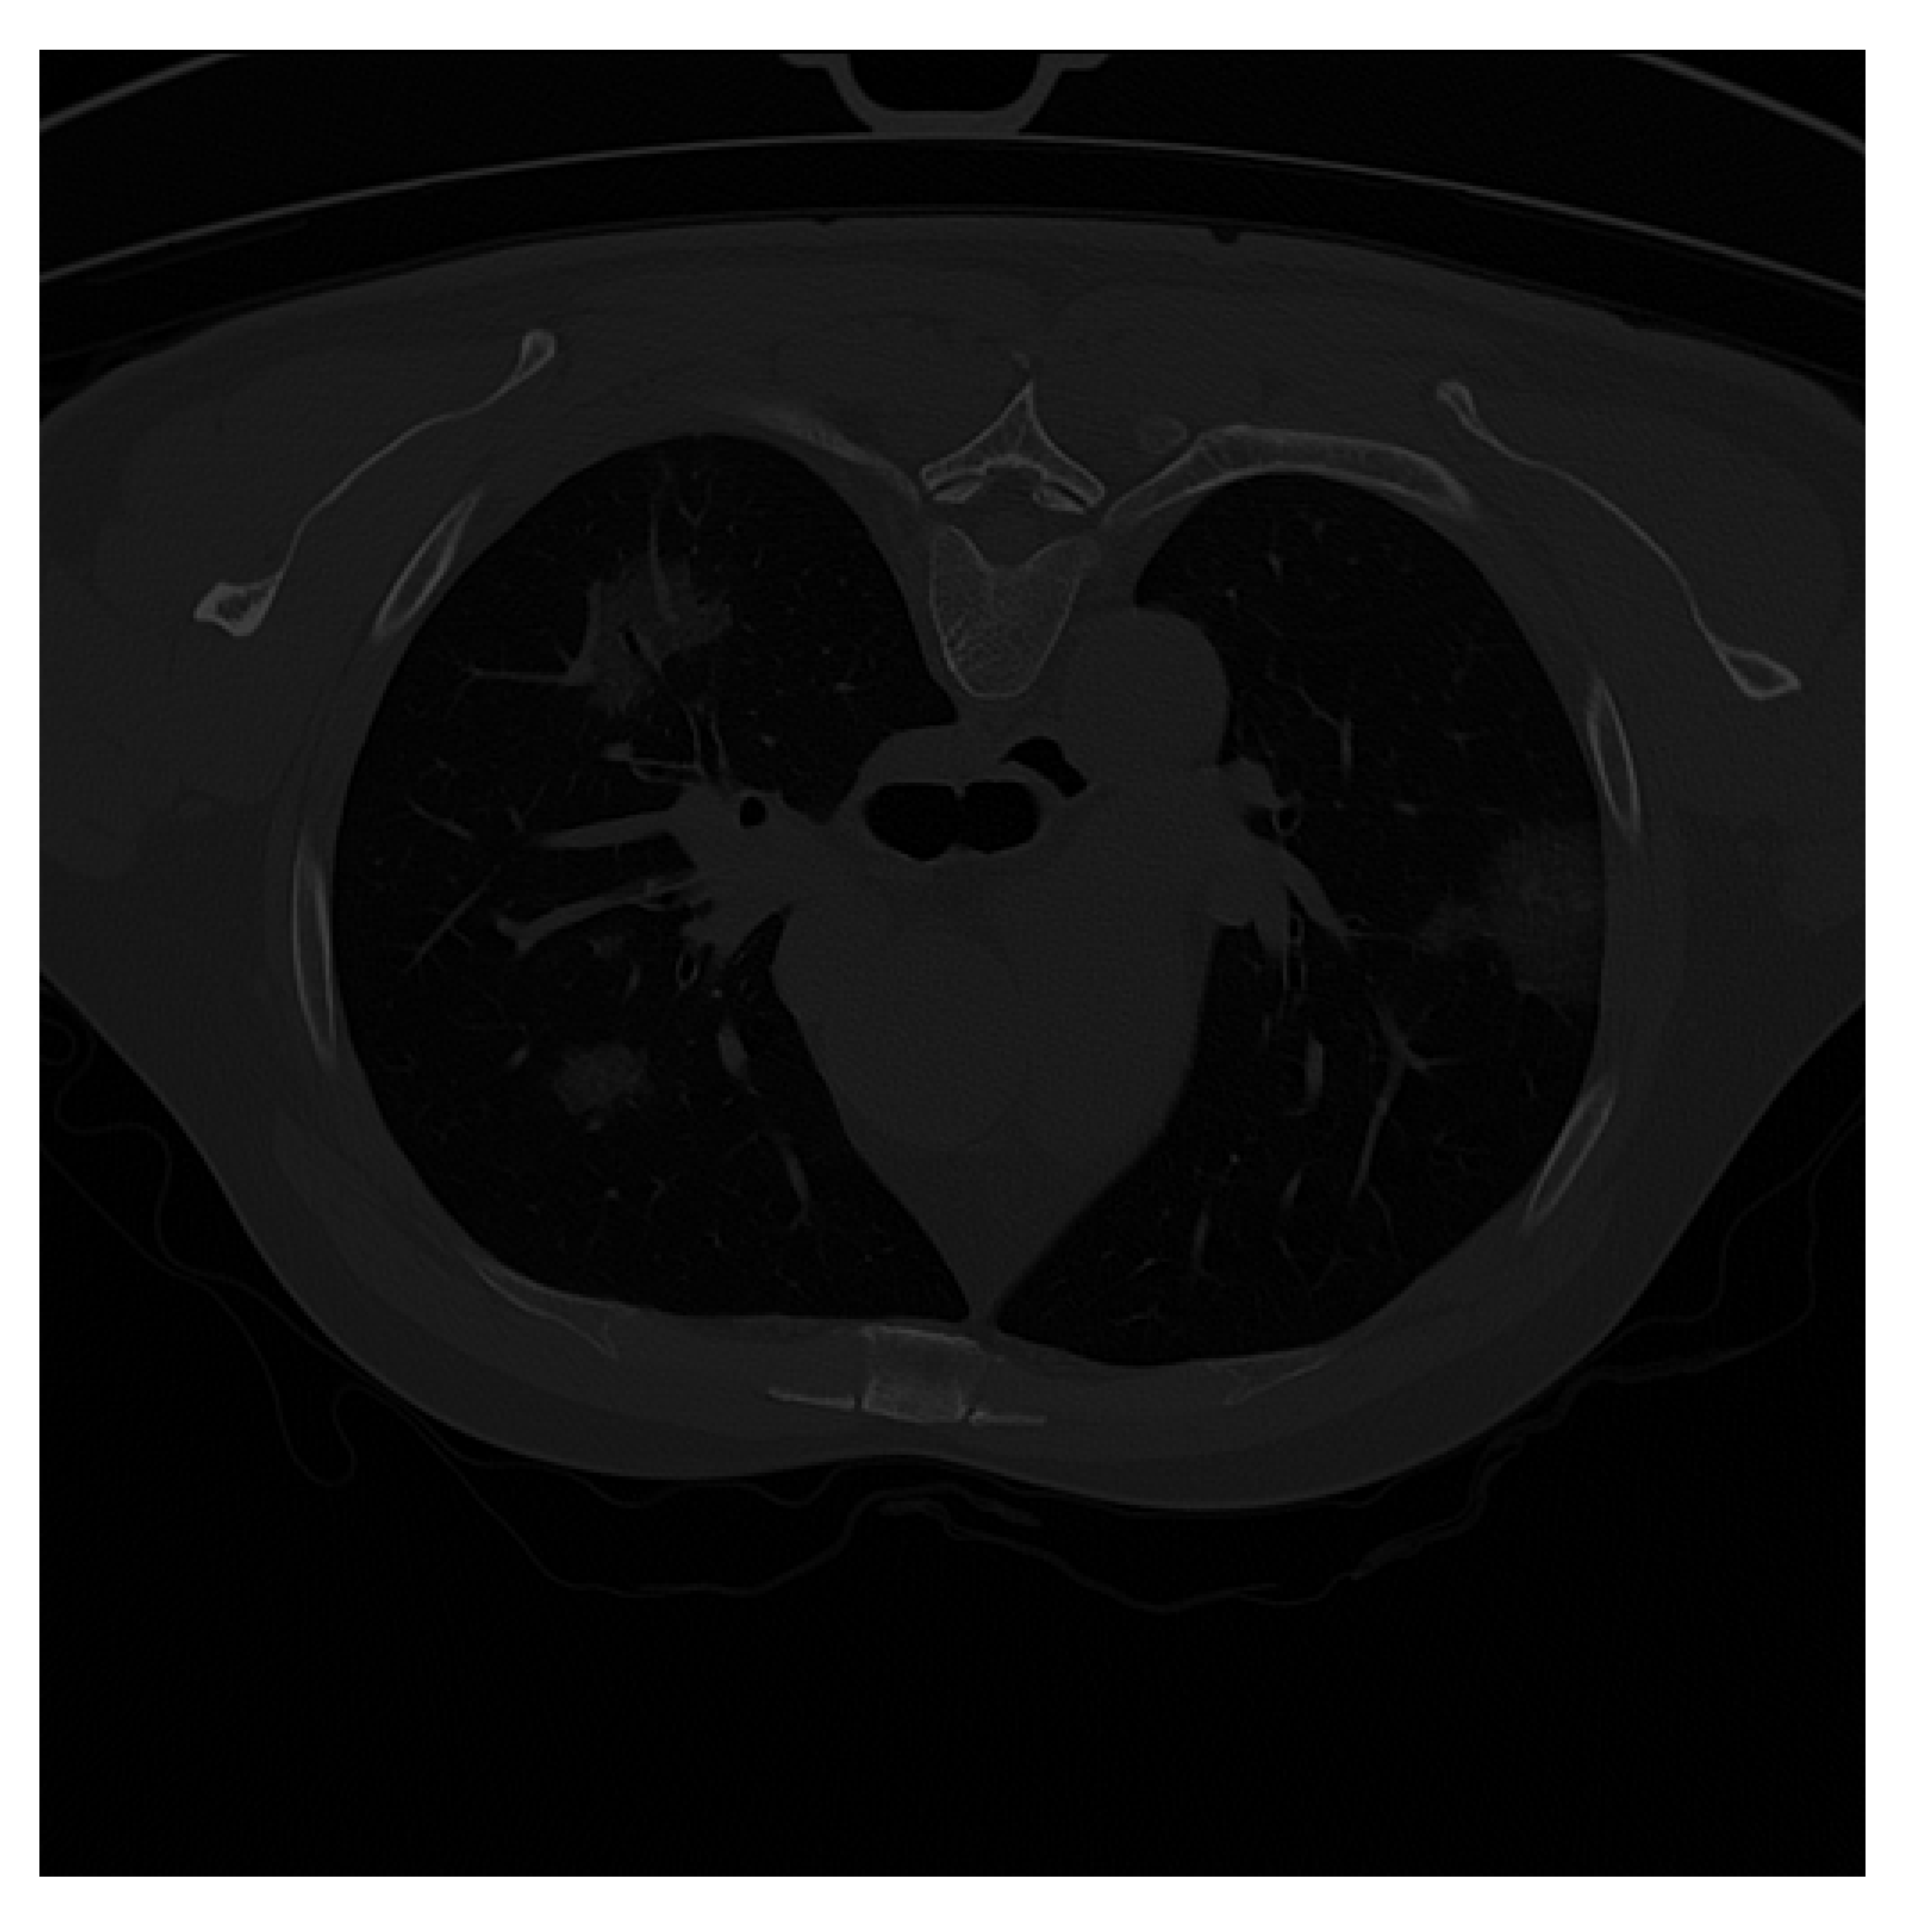

| Original CT Scan | Lung Mask | Infection Mask | Lung and Infection Masks |

|---|---|---|---|

![]() | ![]() | ![]() | ![]() |